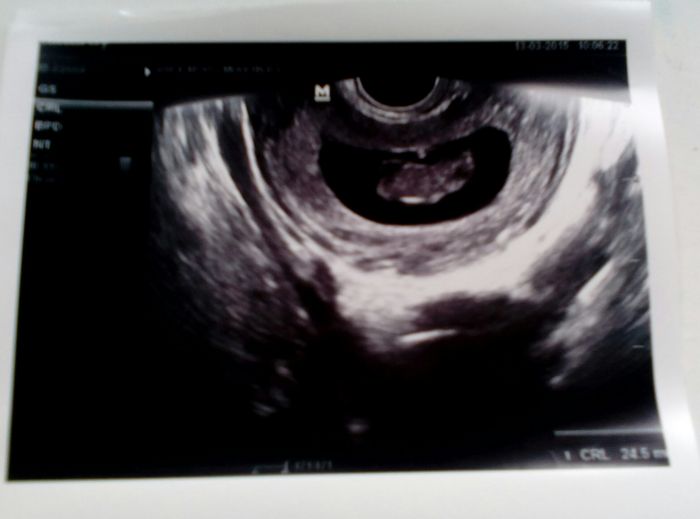

Ahoj holky všechny Vás zdravím a též se k Vám přidávám TP: 11.10. A jsme 9+5 po dnešní kontrole vše vypadá v pořádku fazolka má 25mm tak bude asi maličké po mamince :) ranni nevolnosti naštěstí moc nejsou :) jen občas se mi v práci zamotá hlava, tak mě odvedou na lavičku a po chvilce je to dobré :) jinak všem krásné těhulkování bez nevolností